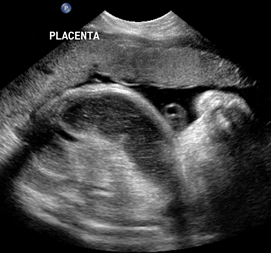

Above. Case 3. 25 4/7 weeks gestation. Sacrococcygeal teratoma. Large mass measuring 5.9 x 10.9 x 8.3 cm, which is noted in the sacral area, but also extends internally superior to the bladder.

Above. Case 3. 25 4/7 weeks gestation. Sacrococcygeal teratoma. Color Doppler indicates the vascular nature of the external portion of this tumor.

Above. Case 3. 25 4/7 weeks gestation. Sacrococcygeal teratoma. Coronal scan demonstrates internal extension of the tumor to the lower abdomen superior to the bladder and within the bounds of the 2 umbilical arteries. This tumor represents a Type 2 sacrococcygeal teratoma (extension to the abdomen).

Above. Case 3. 25 4/7 weeks gestation. Sacrococcygeal teratoma. Transverse of the abdomen demonstrates fetal ascites and likely fetal hydrops.